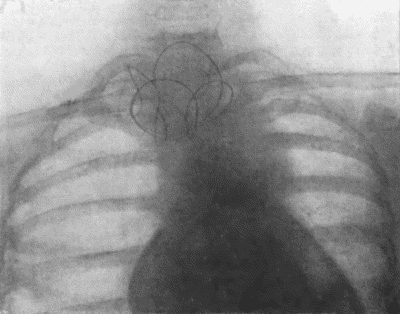

| 62. | Radiogram showing pellets embedded in Arm | 228 |

| 73. | Radiogram of Innominate Aneurysm after Treatment by Moore-Corradi method | 309 |

| 75. | Innominate Aneurysm in a woman | 315 |